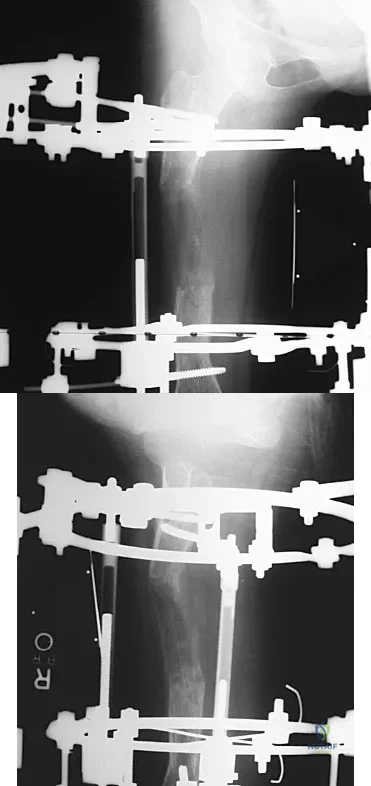

Question 50

Figures 45a and 45b show the AP and lateral radiographs of a 15-year old patient who is undergoing surgery to add 3 cm of length to the femur. Based on the radiographic findings, what is the next most appropriate step in management?

Explanation